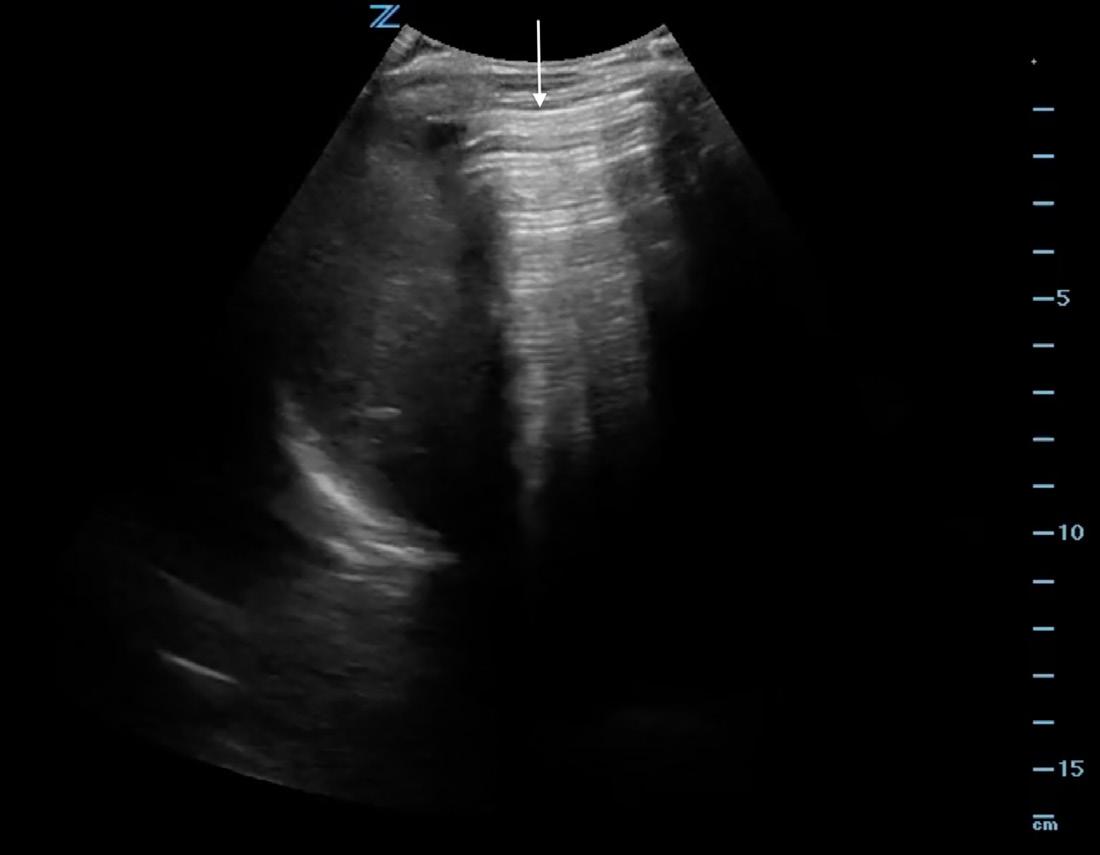

Image 1. Abdominal ultrasound from Case 1 showing free intraperitoneal fluid (thin arrow) as well as free intraperitoneal air (thick arrow) as demonstrated by the enhanced peritoneal stripe sign and reverberation artifact.

Point-of-care ultrasound showed a positive FAST exam (focused assessment with sonography for trauma) with free fluid in the abdomen (Image 1). It also showed a thick peritoneal stripe with posterior reverberation artifacts consistent with pneumoperitoneum and perforated viscus. Computed tomography of the abdomen/ pelvis was expedited, which confirmed the diagnosis of pneumoperitoneum with viscus perforation. Meanwhile, the patient was given intravenous (IV) fluids, broad spectrum antibiotics, and pain control, and was started on vasopressors. Urology and general surgery were consulted immediately, and the patient was taken to the operating room (OR) emergently for exploratory laparotomy.